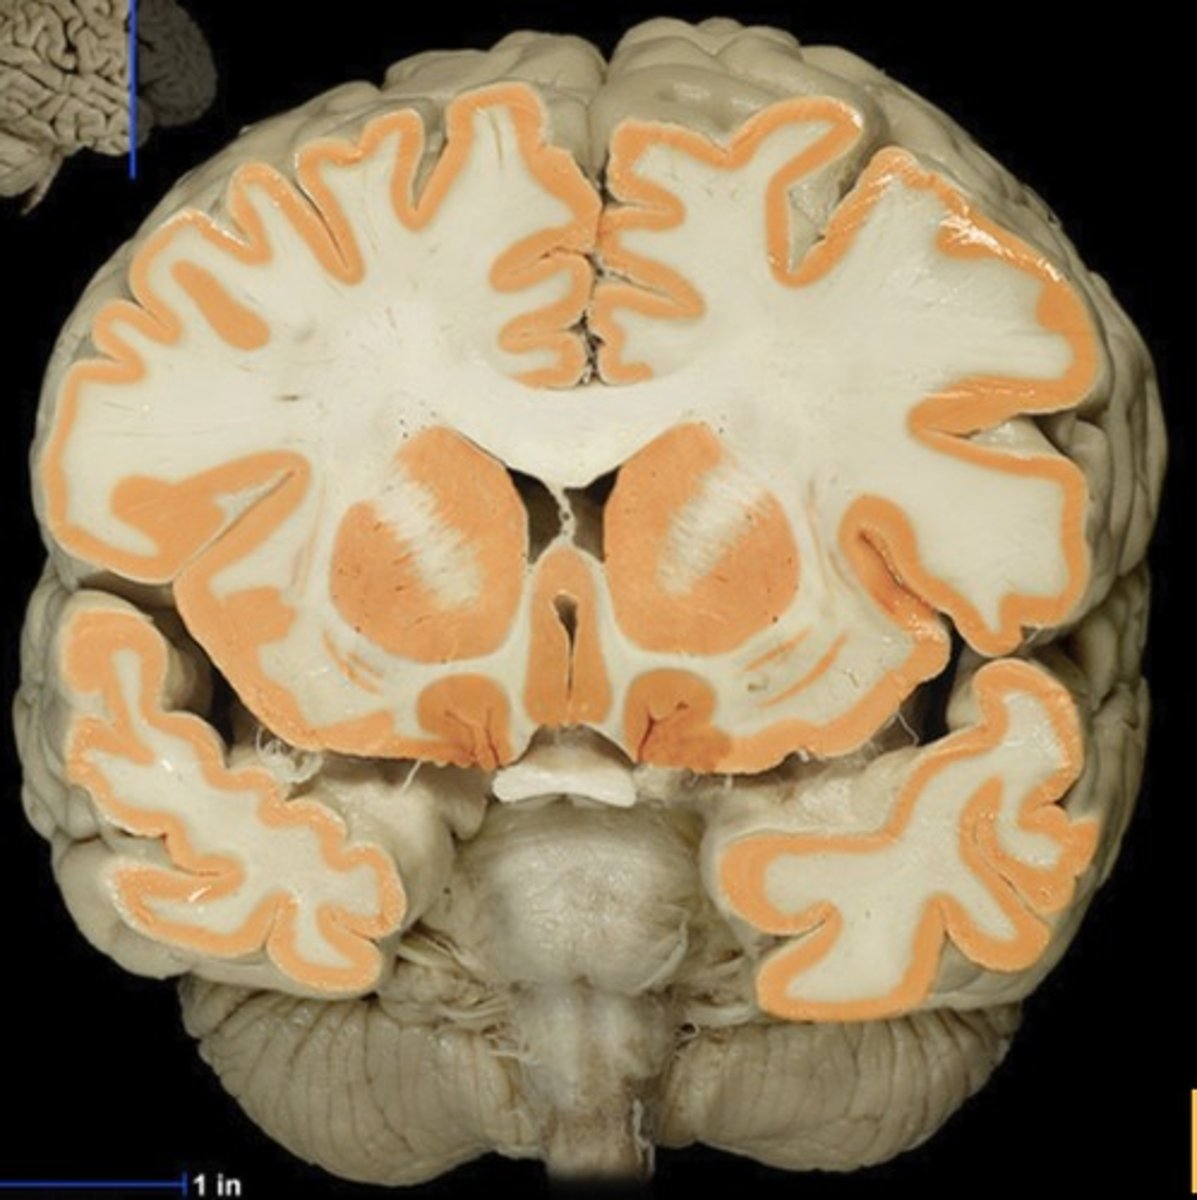

Gray matter

Name this structure

White matter

Name this structure

Gray matter (anterior view of coronal section)

Name this structure

White matter (anterior view of coronal section)

Name this structure